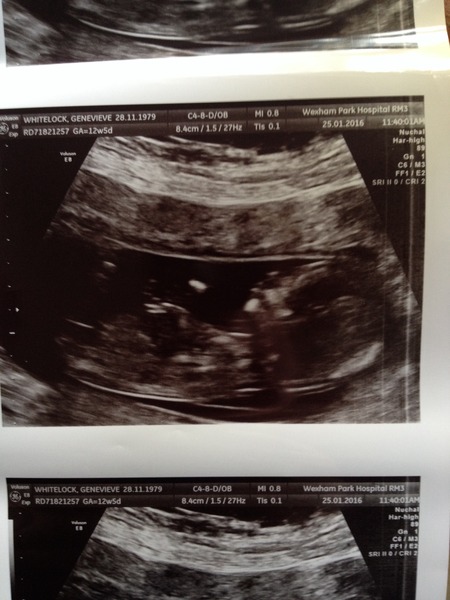

Finally remembered to get my scan pics though, these two were the best

August 2016 (3) - scans fast approaching, teeny tiny bumps appearing, and sickness easing....we hope!

lily yours is so lovely and clear too - what a sweet little profile! hope you're not in hospital too long.

jw and lily, lovely to see your scan pictures, I bet it's all feeling a little more real.

lovely scan pics lily and jw all getting real now!

Lovely pics too lily! Sorry you're still in the hospital, hope you're doing better now.

Lovely scan pics jw and lily, congrats!